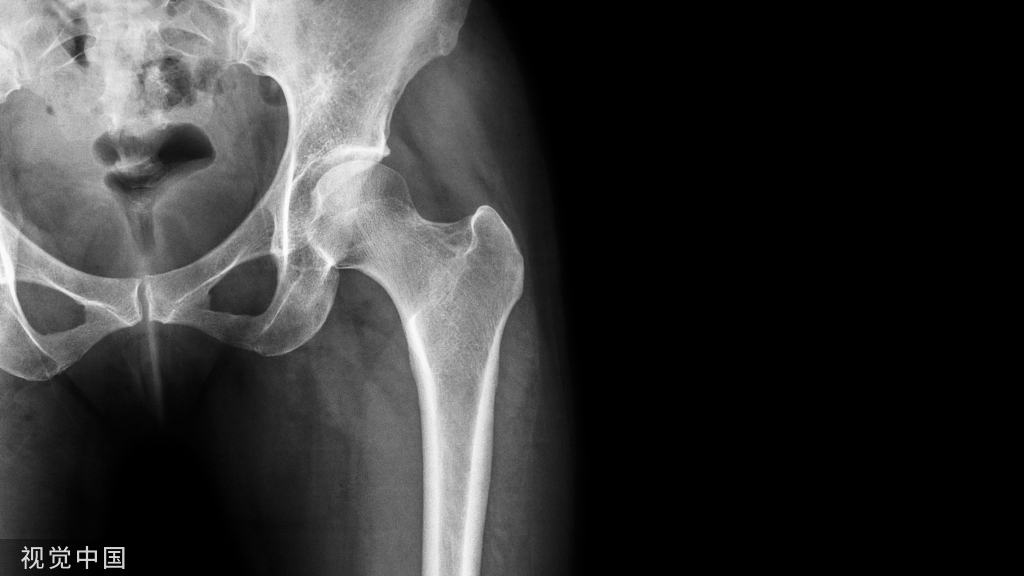

体表标志和切口

1体表标志

髂前上棘位于皮下,一般易于触及,但肥胖患者由于有一厚层脂肪覆盖不易扪清。可用拇指自骨突下向上触摸。

- 大转子是自古骨干和股骨颈结合部向后上方凸起的较大骨块

- 股骨干为股外侧可以触及的股外侧肌内的坚硬结构

- 股外侧肌粗线(股骨粗线)是大转子和股骨干外侧面之间愈合处的粗糙股线,从远端向近端最易触及。在肥胖的患者不能触及。